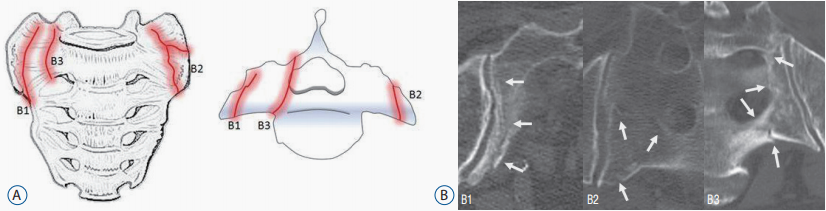

骶骨 B 型骨折

注:B 型-骶骨翼完全骨折 B1-骨折线与骶髂关节平行 B2-骨折线累及骶髂关节 B3-骨折线累及骶孔或骶管

骶骨 C 型骨折

注:C 型-骶骨中央骨折 C1-骨折线从前缘向背侧或骶髂关节移动 C2-骨折线累及单侧骶孔或骶管 C3-横向骨折伴双侧矢状骨折(不稳定)